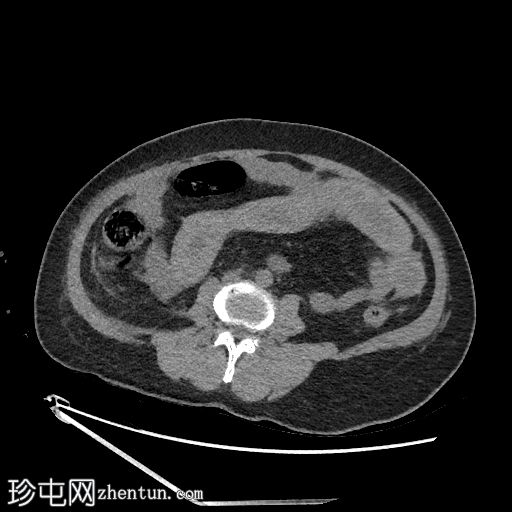

1.jpg

轴位

平扫

空肠(长段,60 cm)肠壁弥漫性节段性增厚。肠壁呈高密度影,平扫CT值约为56 HU,并可见强化。

可见肠系膜水肿和血管充血,以及少量腹水。

肠系膜上动脉和静脉通畅,未见血栓。

影像学表现最提示黏膜下出血。

鉴别诊断包括感染性肠炎。